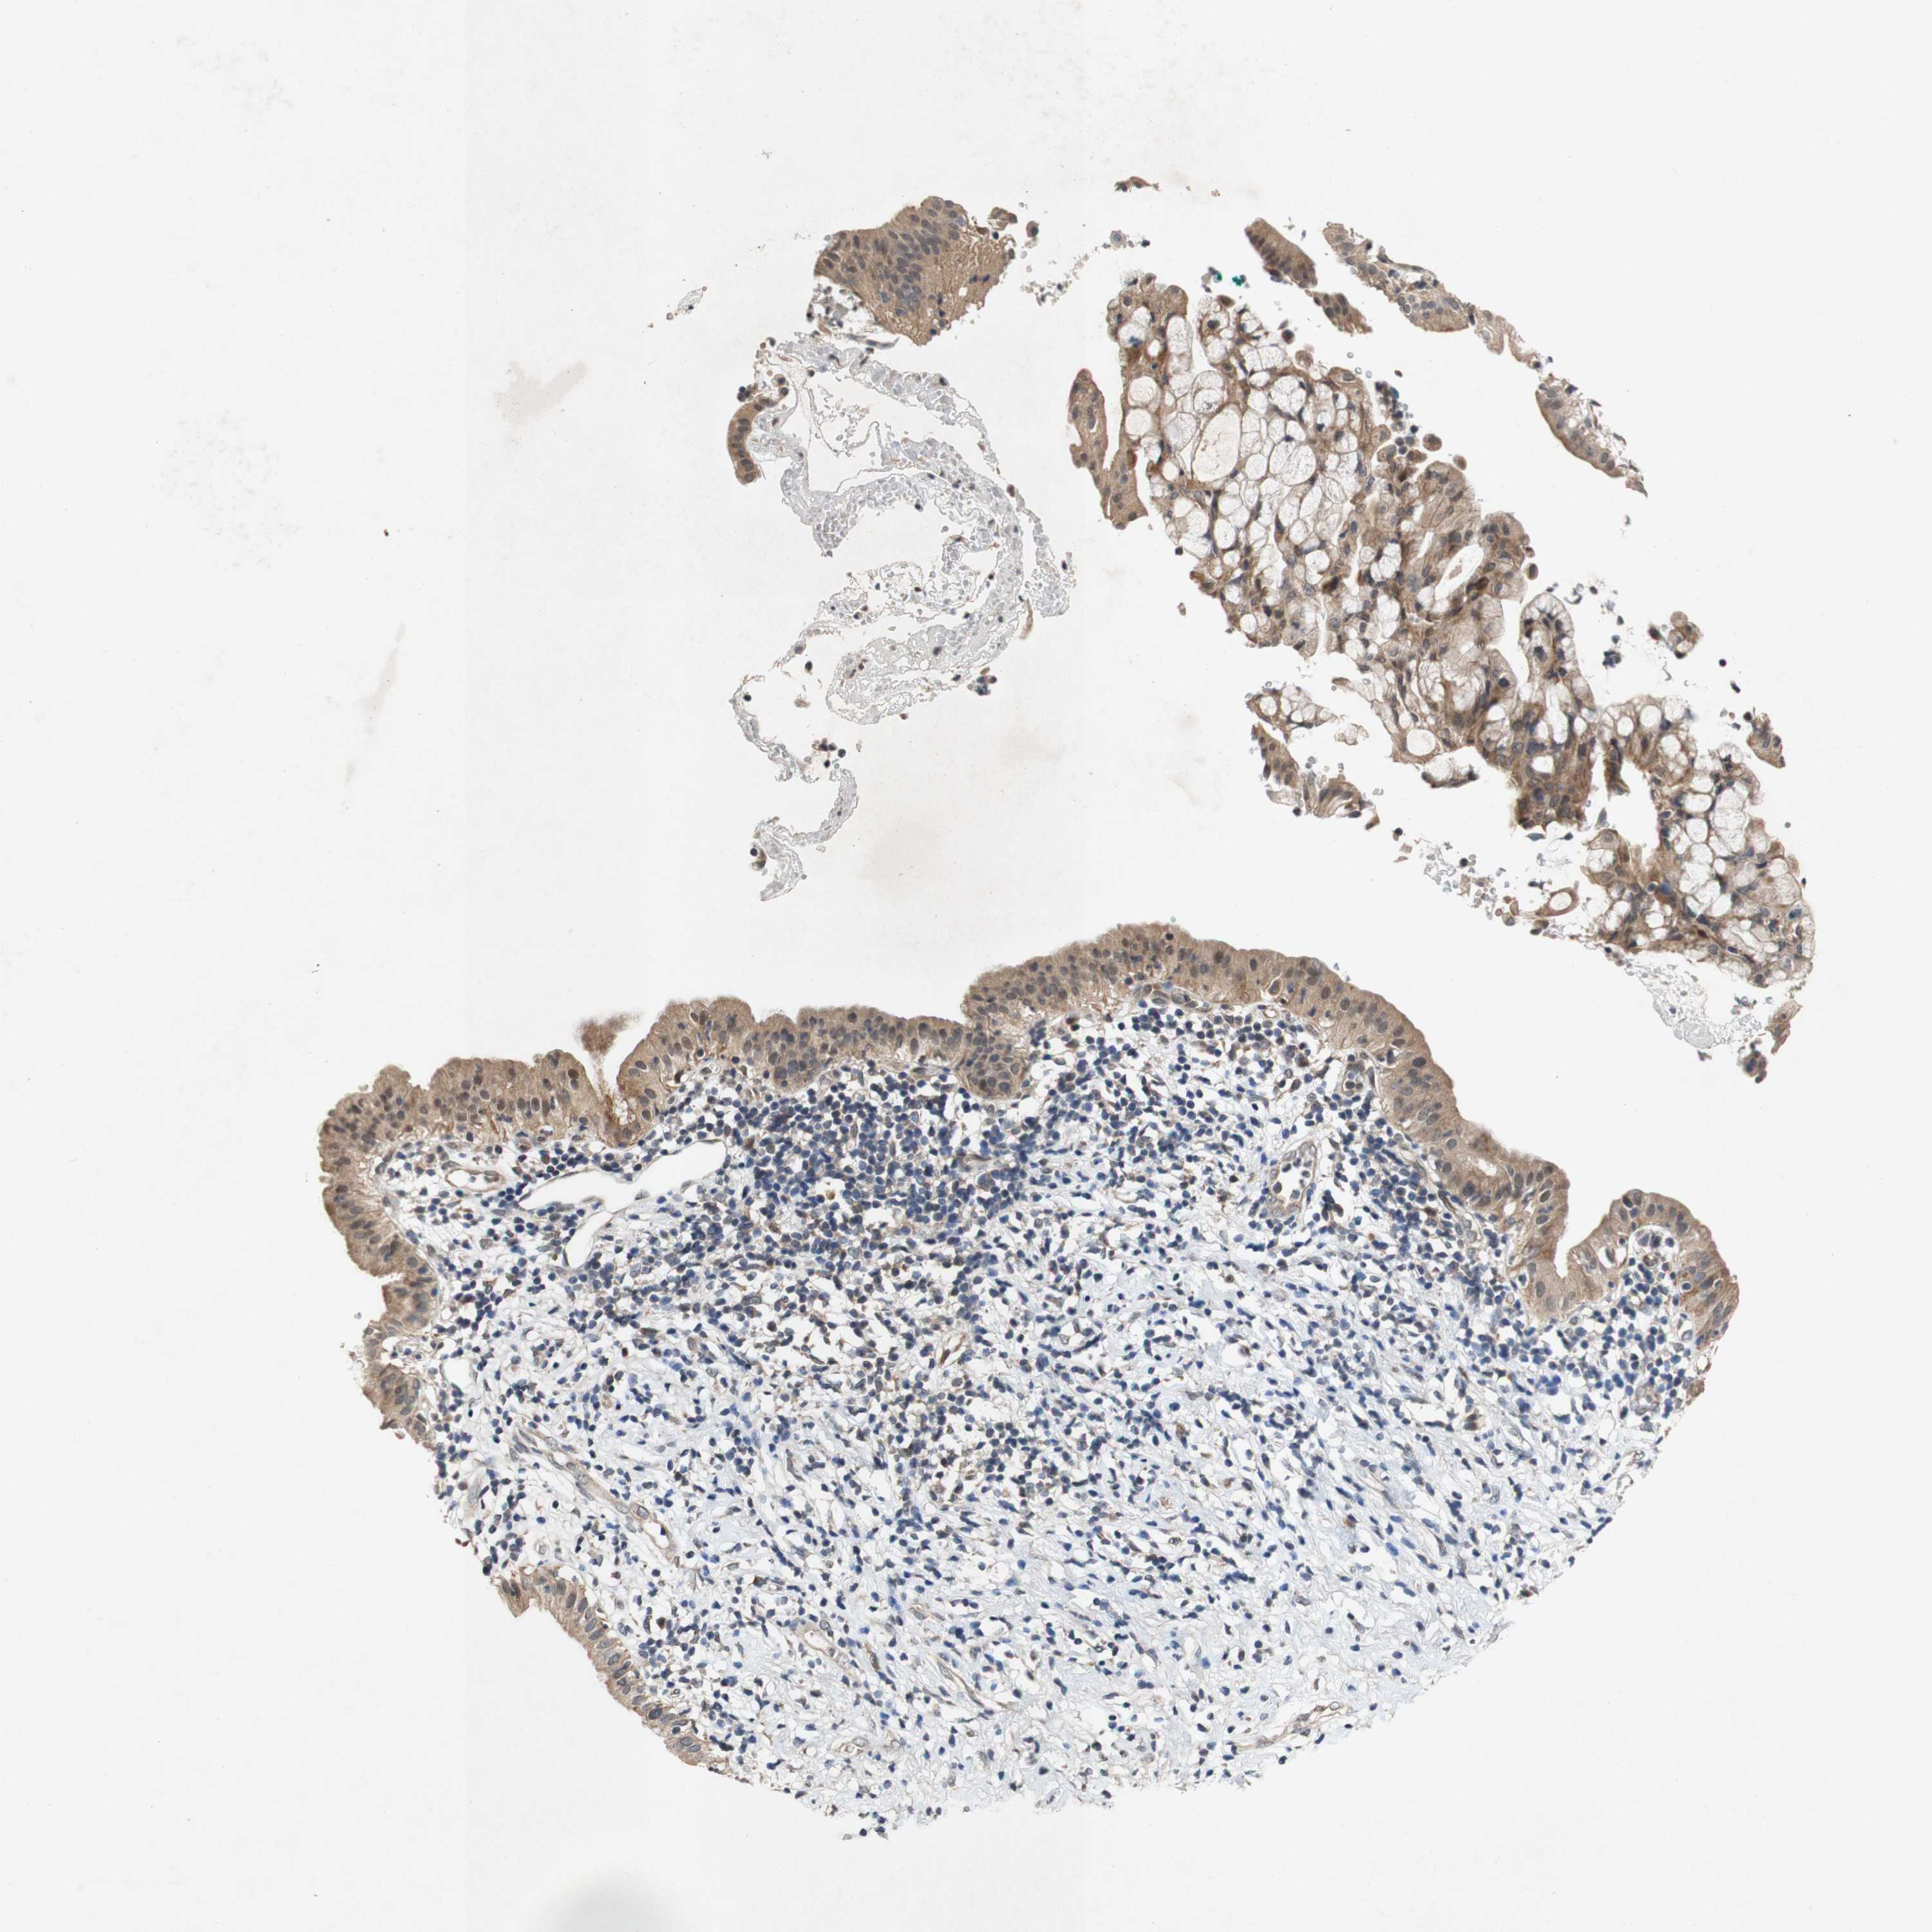

PANCREATIC CANCER - Protein expressioni

A mouse-over function shows sample information and annotation data. Click on an image to view it in a full screen mode. Samples can be filtered based on level of antibody staining by selecting one or several of the following categories: high, medium, low and not detected. The assay and annotation is described here.

Note that samples used for immunohistochemistry by the Human Protein Atlas do not correspond to samples in the TCGA dataset.

Antibody stainingi

Antibody staining in the annotated cell types in the current human tissue is reported as not detected, low, medium, or high, based on conventional immunohistochemistry profiling in selected tissues. This score is based on the combination of the staining intensity and fraction of stained cells.

Each image is clickable and will lead to virtual microscopy that enables deeper exploration of all samples and also displays staining intensity scores, fraction scores and subcellular localization as well as patient and tissue information for each sample.

Antibody CAB004528

Antibody CAB009326

Adenocarcinoma, NOS

Adenocarcinoma, metastatic, NOS